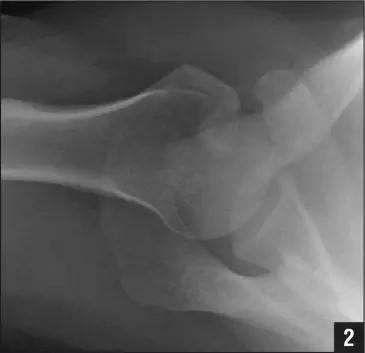

病例 1:一般股骨髁间、髁上粉碎骨折中含 Hoffa 骨折的不少见,但单纯后髁骨折则很少见。

正位片

侧位片

水平位 CT